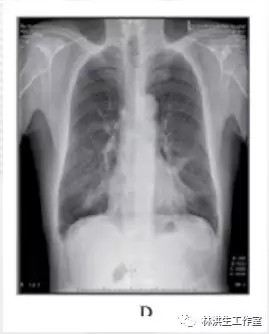

服药 1周后瘙痒减轻,皮疹减少,2个月后复查胸片提示肿瘤稍有缩小,之后继续按原方加减服用中药治疗,定期复查胸片提示肿瘤呈逐渐缩小趋势,同时瘙痒逐渐减轻明显,全身皮疹亦明显好转。2016年6月复查胸片,肿瘤明显缩小,仍有轻微瘙痒、已无皮疹。

D: 2016 年 6 月 23 日复查双侧肺肿物较发病时明显缩小。